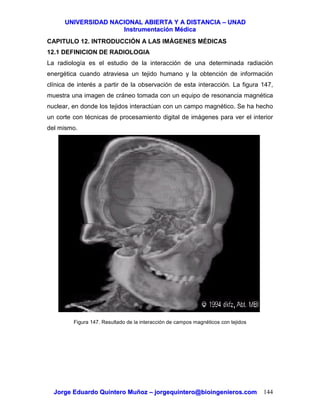

5.5 DISEÑO DE UN TERMOMETRO CLINICO

La figura 62 muestra el diagrama de bloques del módulo de temperatura de un